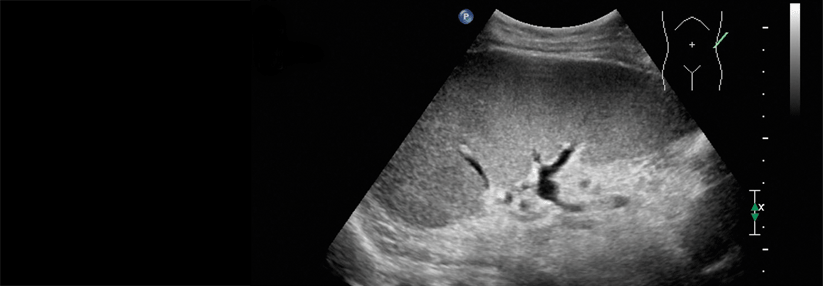

Die wAIHA zeigt sich mit niedrigem Hb und IgG-Antikörpern sowie therapeutischen Unterschieden zur Kälteagglutininerkrankung. Die wAIHA zeigt sich mit niedrigem Hb und IgG-Antikörpern sowie therapeutischen Unterschieden zur Kälteagglutininerkrankung. © BillionPhotos.com – stock.adobe.com

Die autoimmunhämolytische Anämie vom Wärmetyp präsentiert sich unter anderem mit niedrigen Hb-Werten und Wärmeantikörpern vom Typ IgG. Ein Experte erläuterte, wie die Notfalltherapie aussieht und wo die Unterschiede zur Kälteagglutininerkrankung liegen.

Ein 47-jähriger Patient stellt sich in der Notaufnahme mit einem Hämoglobin(Hb)-Wert von 4,5 g/dl vor, inklusive unter anderem Luftnot, Belastungsintoleranz und Blässe – also ein Notfall, denn sinkt die Hb-Konzentration unter 6 g/dl, bestehe das Risiko einer Koronarischämie, hob Dr. Wolfgang Blau, Helios Dr. Horst Schmidt Kliniken, Wiesbaden, hervor. Auffällig waren zudem eine Laktatdehydrogenase von ca. 1.300 und ein Bilirubinwert von 7,0. „Da hat man schon einen gewissen Hinweis für die Hämolyse“, so der Kollege.